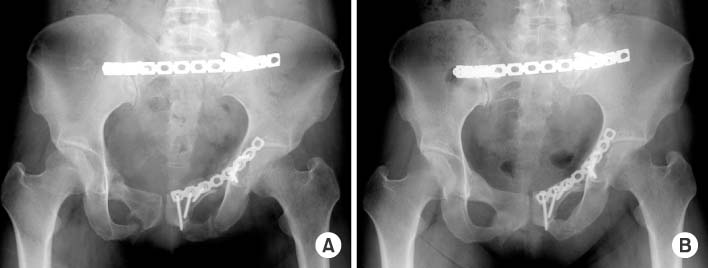

(A) Immediate postoperative pelvis anteroposterior radiograph shows correction of superior migration and internal rotation of the left hemipelvis. (B) Radiograph taken four years after reconstruction shows a well united osteotomy site without complications.

Fig. 6 (A) Immediate postoperative pelvis anteroposterior radiograph shows correction of superior migration and internal rotation of the left hemipelvis. (B) Radiograph taken four years after reconstruction shows a well united osteotomy site without complications.